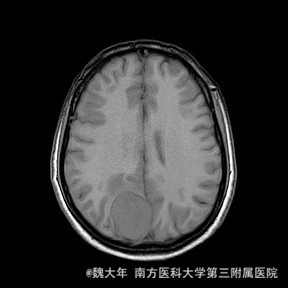

52岁,女性,因“反复头痛10余年,加重1年”入院。患者10余年前无明显诱因始出现头痛,表现为全头发作性胀痛,反复发作,无伴头晕、恶心,无呕吐、肢体抽搐,自行服药(具体不详)及休息后缓解,未予特殊处理。1年前患者觉头痛逐渐加重,以右顶部为甚,劳累或日晒后加重,无头晕、视物旋转,无恶心、呕吐,无发热、寒战,休息或平躺后症状稍有缓解,自行服药不能改善,至当地医院就诊,查颅脑MRI和CT提示“右侧顶部脑膜瘤”。

查体:神清语利,反应灵敏。记忆力、计算力、定向力、理解力均未见异常。双侧瞳孔等圆等大,直径约2.5mm,光反射灵敏,眼球活动好,视野粗测无明显缺损。伸舌居中,余颅神(-)。颈软,无抵抗。四肢肌力、肌张力正常,左下肢感觉稍减退。生理反射存在,病理反射未引出。小脑共济失调征(-)。